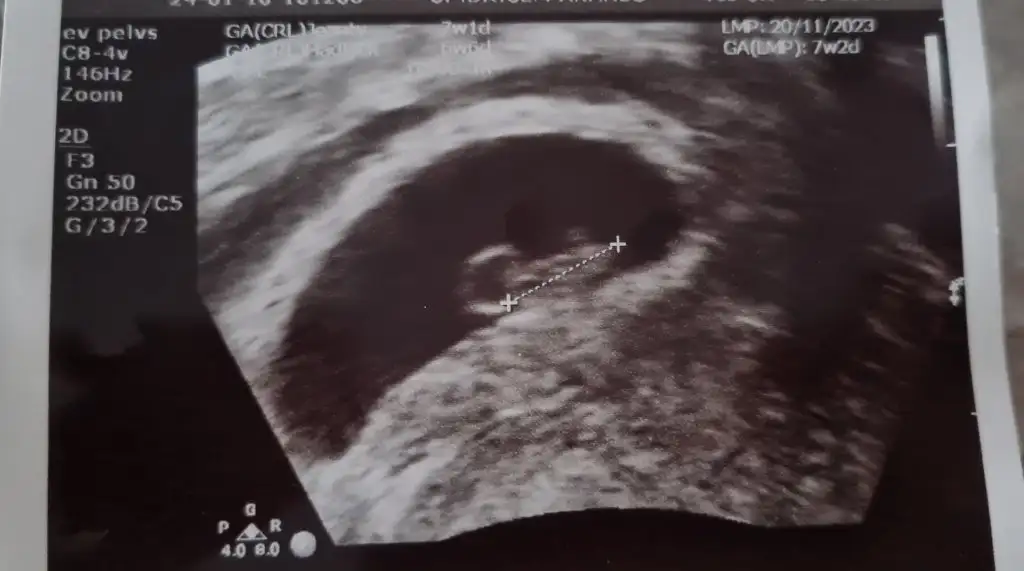

Geçmiş olsun öncelikle ben de aynı durumu yaşadım kanama alanım 1cm di kese altında sizin kaç cm alanı ve nerde ?arkadaslar merhabaalar yasayan varsa bi yardimci olabilirmisiniz 9 aralikta 5. gun embiriyosu transferi oldum taze transfer suan 7+4 teyiz 5+4te yolku gorduk bebisi ve kalbi duyucaktik carsamba gunu 7+2 ken ama sali gunu gece ani bi kanamayla hastaneye gittik adet kanamasi gibi ama temiz kan renginde yogun bi kanamam oldu ve hem kucuk hemde asiri buyuk el kadar ve avuc ici kadarda degisen kocaman cigere benzer pihtilar geldi ama agri sizi yoktu kalp atisini duydum gelisiminede iyi dedi ama kanama alanim cok buyukmus gorsel ekliyorum ben yumurta toplamadan beri progestan 200 luk fitil seklinde gunde 3 tane aliyodum simdi progestan dex ekledi gunde 1 kere seklinde benim gibi durum yasayip gecen var mi kalbim sıkışıyo o kadar kahroldum ki olumlu dusunemez oldum

altinda falan diye bi ibare yapmadi ama resim ekledim ilk resimde kesenin saginda tarali alan boyutta 4.2cm uzunlukta genislik 1.35cm doktorum dediki hastalar kanamadan korkar ama ben kanamasini severim cunku icerde basinc olusturmaz dedi kanama biraz kesildi gibi 2. gun temiz kan ara ara yine geliyodu ama bugun hep eski kan seklinde nokta gibi geldiGeçmiş olsun öncelikle ben de aynı durumu yaşadım kanama alanım 1cm di kese altında sizin kaç cm alanı ve nerde ?